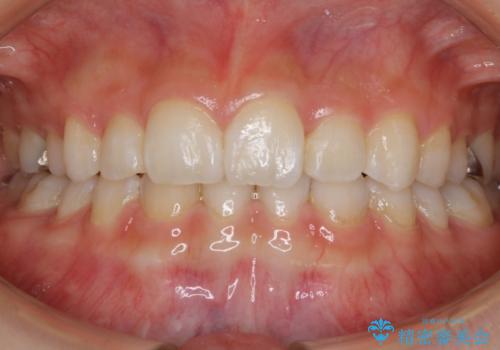

【抜歯】口元を引っ込めたい ワイヤー矯正

- 20代 女性

- ワイヤー(クリア装置)

- 2年6ヶ月

- 30回以上

しっかりと口元・顔貌まで変化を起こせるように上下左右の第一小臼歯を抜歯し、ワイヤー装置にて矯正を開始することとなりました。

- 税込¥990,000 (ワイヤー装置+マイクロインプラント費用)費用は治療当時の料金となります